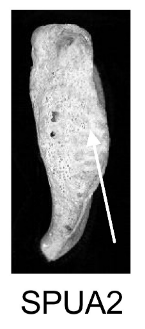

Demi-face postérieure (SPUA)

Changements morphologiques de la demi-face postérieure de la symphyse pubienne, incluant la présence et l'orientation de crêtes et sillons, et le processus de remodelage osseux.